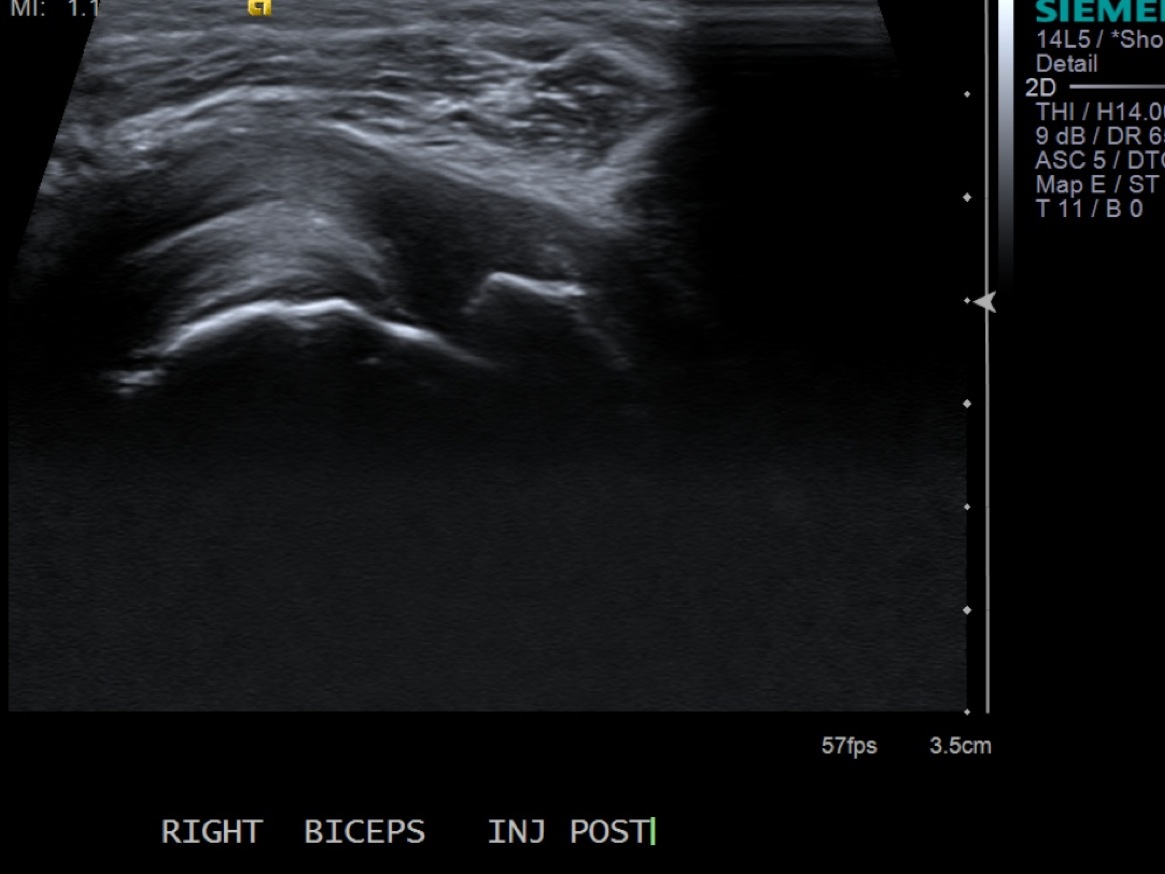

12. Scan sheath to demonstrate distention.

• descriptiondescription